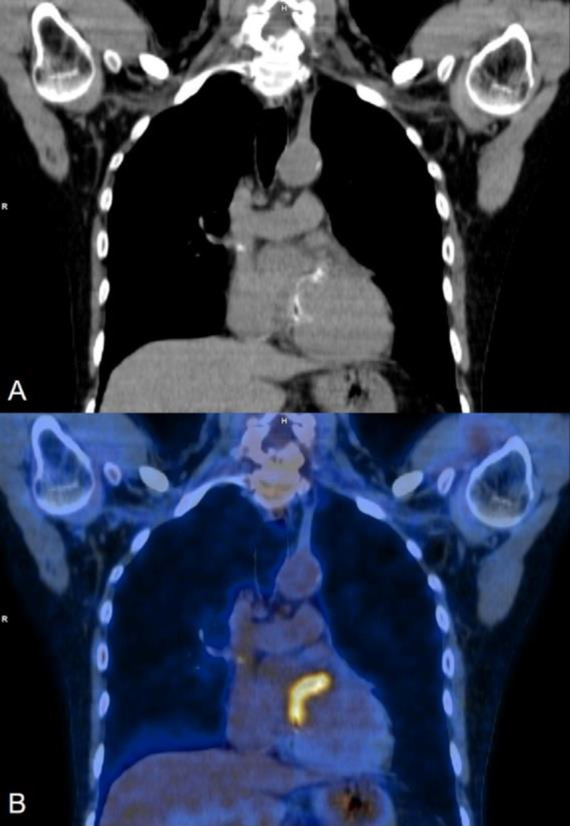

随着介入心脏病学手术数量的增加,心脏设备感染(包括起搏器、人工瓣膜、冠状动脉和主动脉支架)的数量也在增加。这些感染会导致严重的发病率,如果处理不及时甚至会导致死亡。如果临床上怀疑有心脏装置感染,第一线影像检查方法是经胸超声心动图,经食道超声心动图也可用于特定病例。心脏设备感染的确诊大多需要借助血液或脓液培养。尽管超声心动图是一种非常有效的心脏评估技术,但它无法区分感染与血栓或纤维化。随着正电子发射计算机断层扫描(PET CT)机在全球范围内的普及,18F-FDG PET CT 在感染成像中的应用越来越受到重视,尤其是在心脏设备感染方面。最近的大多数研究表明,18F-FDG PET CT 具有良好的诊断准确性,许多最新的诊断和管理指南都承认了它的作用,尤其是在诊断不明确的病例中。我们介绍了六个这样的病例,在这些病例中,18F-FDG PET CT 为疑似心脏设备感染患者的诊断、确诊感染的存在、划定感染范围、治疗反应,有时甚至帮助做出适当的治疗决策提供了有价值的信息。

With the increasing number of interventional cardiology procedures, the number of cardiac device infections (including pacemakers, prosthetic valves, coronary and aortic stents) have also increased. These infections can cause significant morbidity and can even lead to mortality if not managed promptly. If suspected clinically the first-line imaging modality is Trans-Thoracic Echocardiography, while Transesophageal Echocardiography is also used in selected cases. The confirmation of a cardiac device infection is mostly done with the help of blood or pus culture. Even though Echocardiography is a very efficient technique for the evaluation of the heart, it cannot differentiate infection from thrombus or fibrosis. With the increasing availability of Positron Emission Tomography CT (PET CT) machines worldwide, the use of 18F-FDG PET CT for infection imaging has gained traction, especially for cardiac device infection. Most of the recent studies show a good diagnostic accuracy of 18F-FDG PET CT with many of the recent diagnostic and management guidelines now acknowledging its role, especially in equivocal cases. We present six such cases where 18F-FDG PET CT provided valuable information either for diagnosis, confirming the presence of infection, delineating extent, therapy response or sometimes even helping appropriate treatment decision making in patients with suspected cardiac device infection.